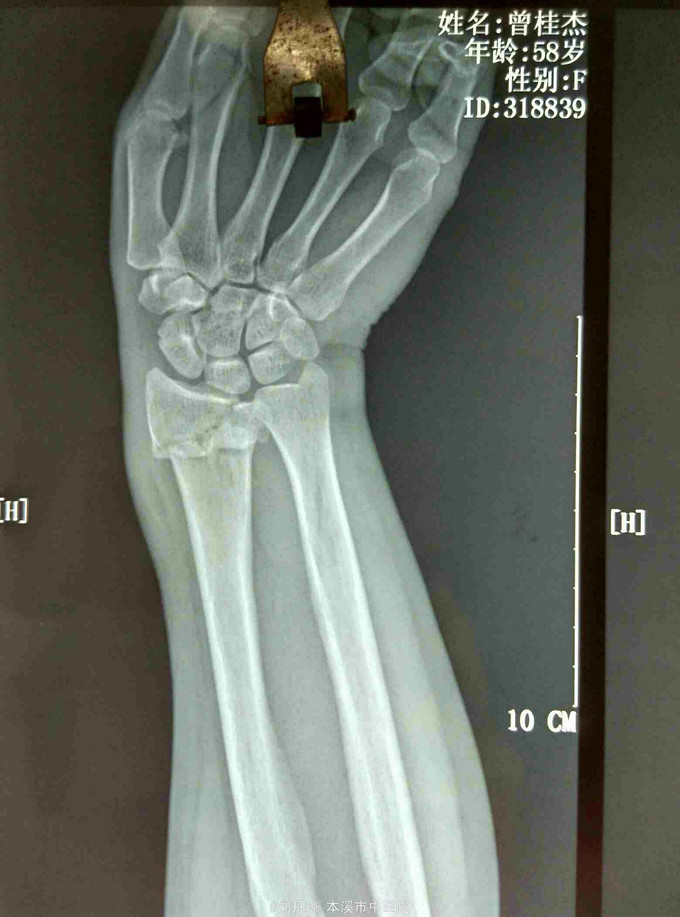

主诉:左腕刺痛,活动受限3小时。 病史: 患者3小时前不慎摔伤腕,伤后左腕刺痛,活动受限。遂来我院门诊求治。

诊断: 左colles骨折 治疗:手法整复,夹板固定,中药外用,接骨续筋中药口服。

随访|年。摔倒时腕关节极度背伸,使前臂旋前的扭力向前运动,导致此型骨折。colles 骨折占前臂骨折的75%,多见于中老年女性。colles骨折是最常见的骨折。典型表现为餐叉状畸形。主要包括然后远端向背侧移位和倾斜,桡偏,桡骨短缩,骨折常涉及桡腕关节和下尺桡关节。尺骨茎突骨折也是常见的合并损伤。